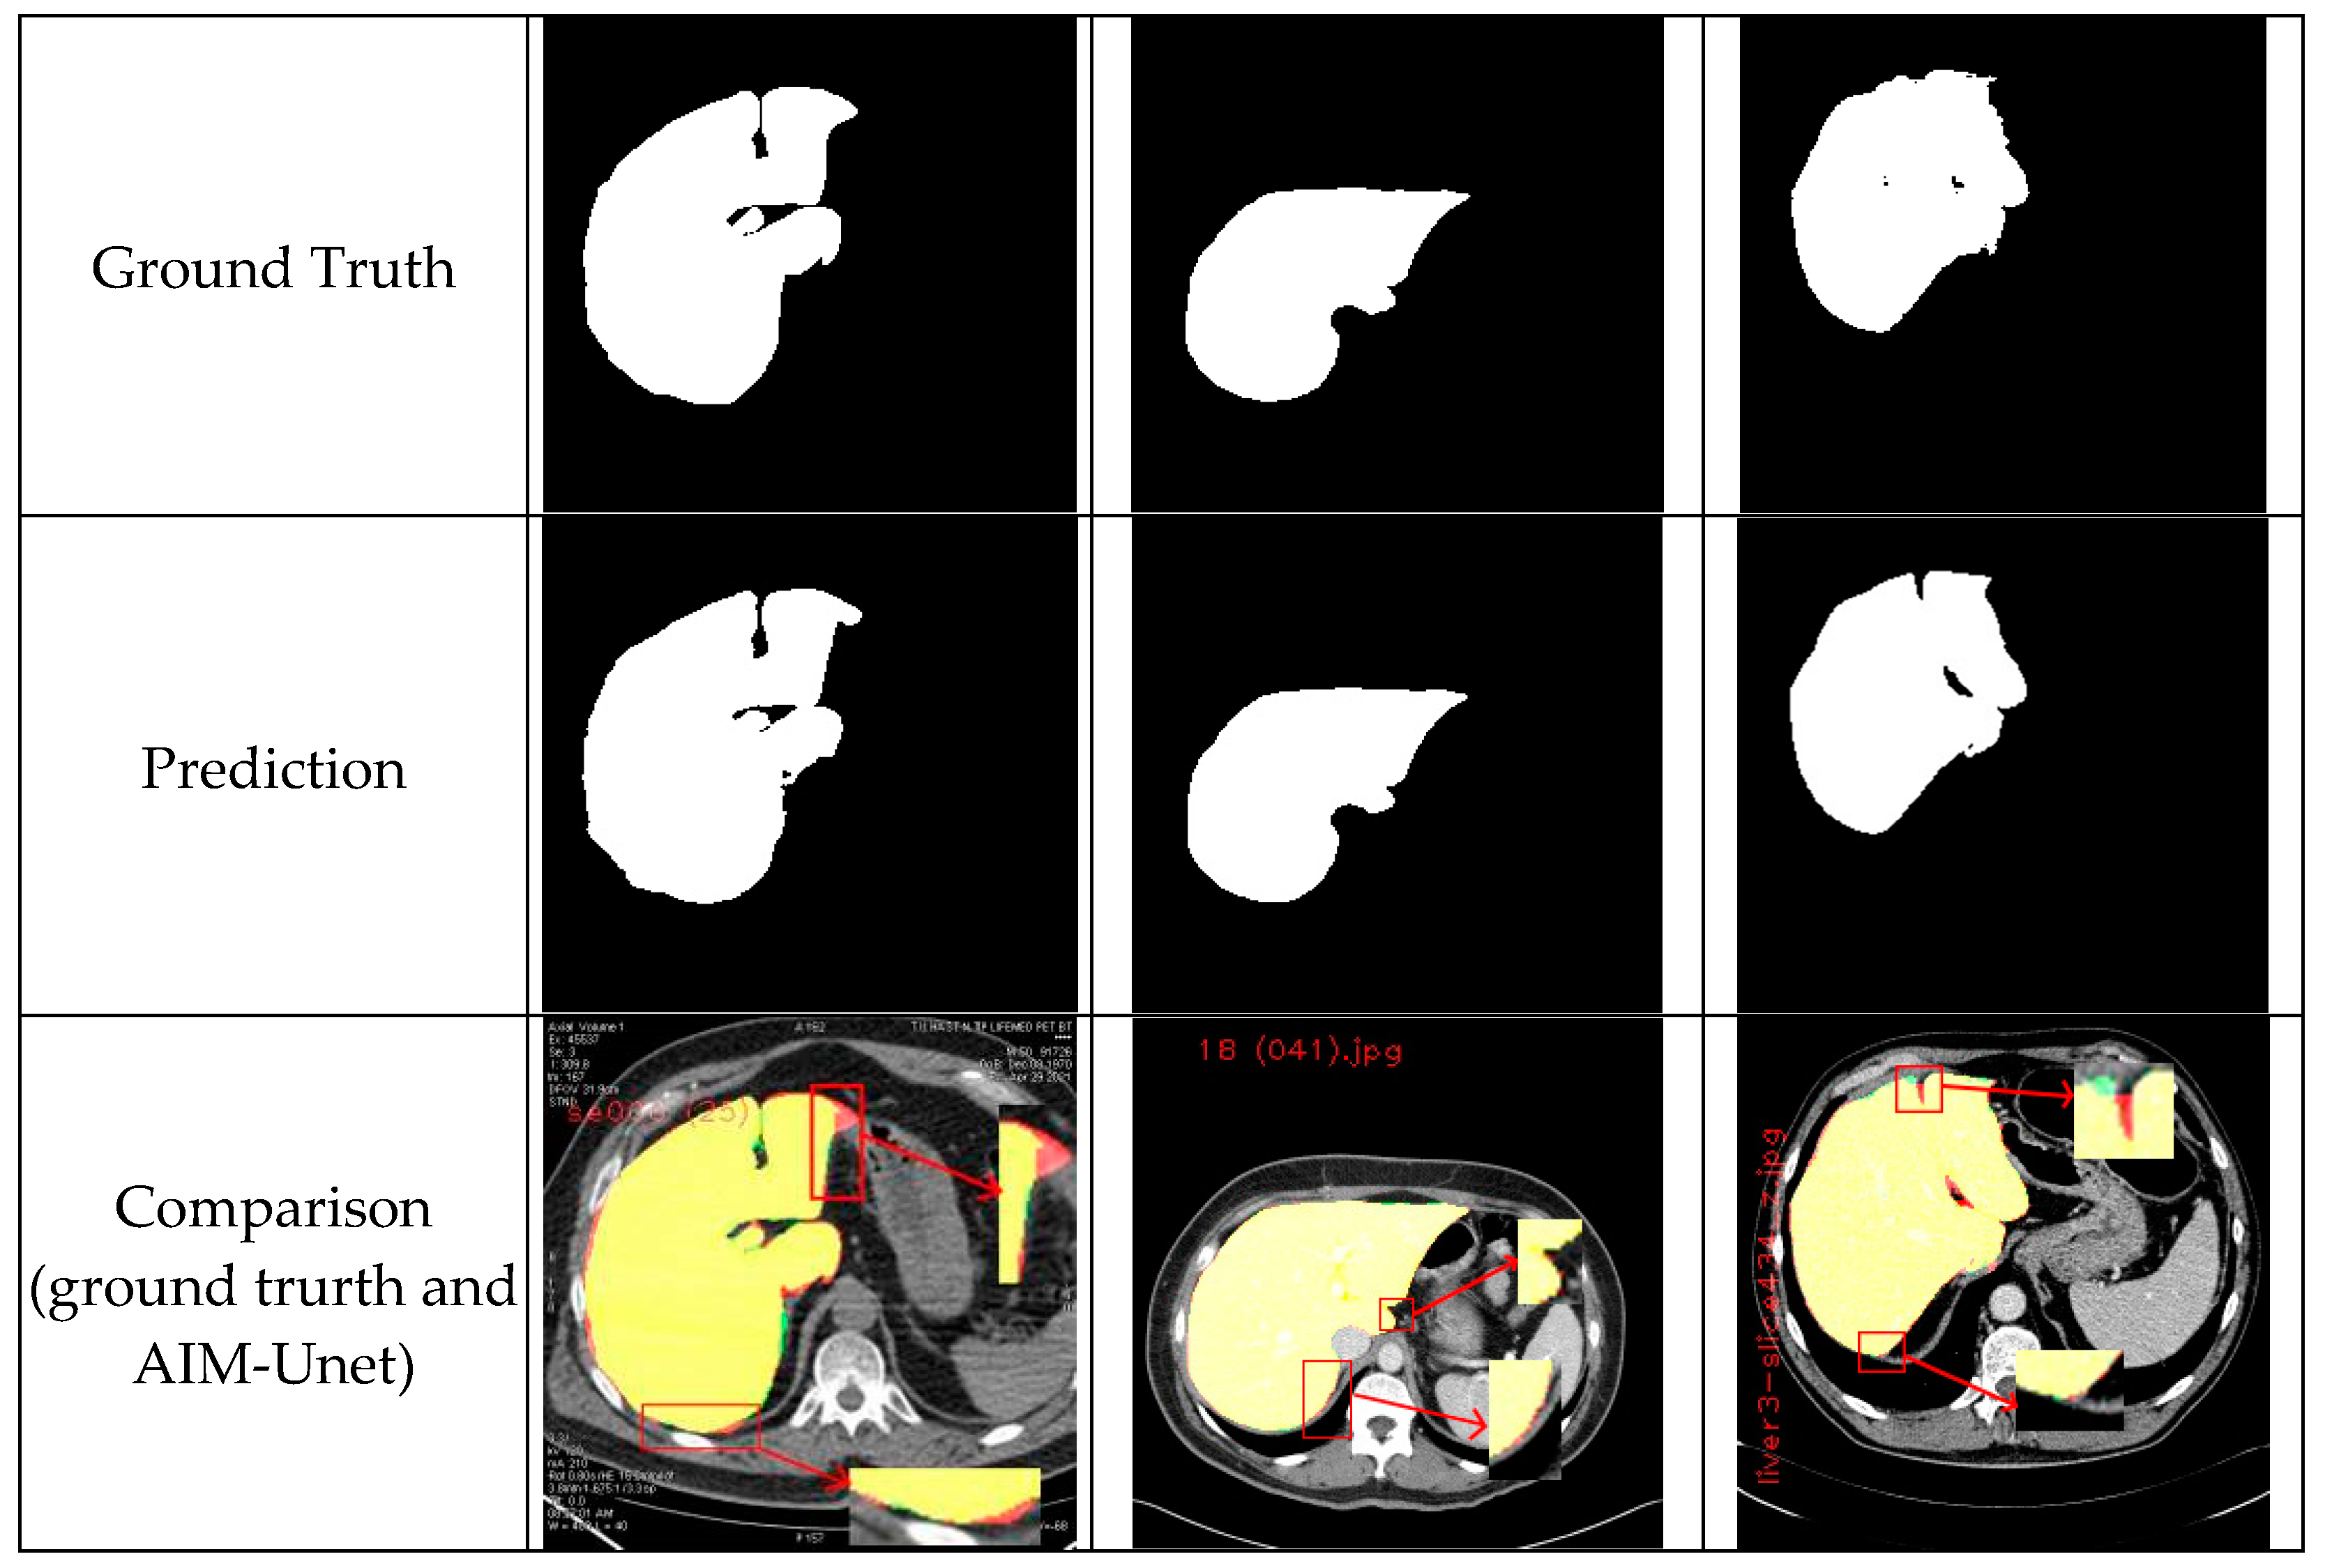

Fully Automatic Liver and Tumor Segmentation from CT Image Using an AIM-Unet